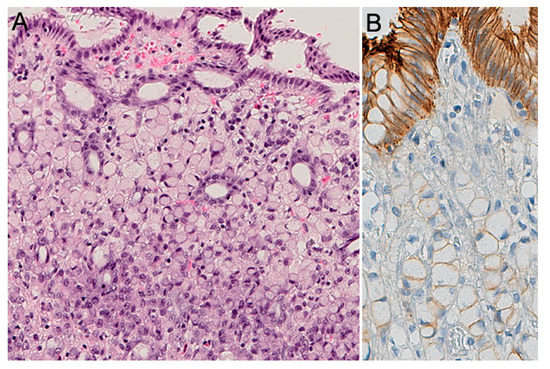

2.5. Histochemical and Immunohistochemical Stains